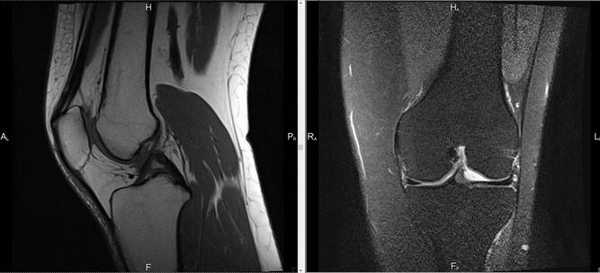

Снимок МРТ коленного сустава

Индукционное поле, используемое при МРТ, не несет лучевой нагрузки. Под действием магнита меняется положение молекул воды в клетках, возникает резонанс, считываемый чувствительными датчиками. Информация поступает на монитор компьютера в виде послойных фотографий сканируемой зоны.